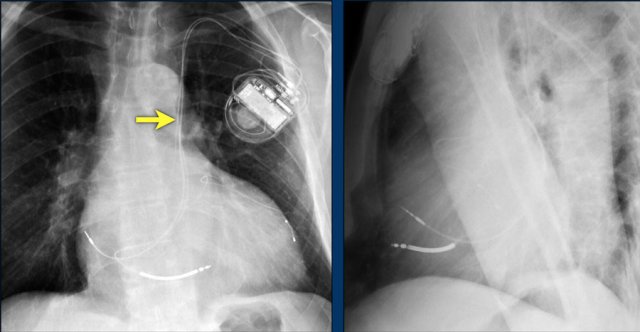

This patient has three valves repaired:

• Mitral

• Tricuspid

• Aortic

There is a pacemaker with epicardial leads.

This was done, because it was thought that a normally placed lead to the right ventricle would interfere too much with the function of the tricuspid valve prosthesis.

White arrow points to aortic valve.

Yellow arrow points to mitral valve.